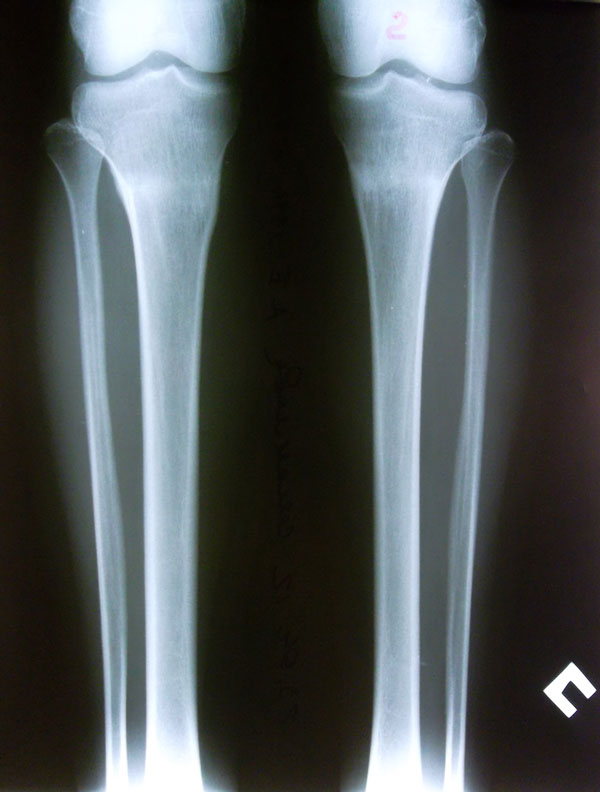

- Диагноз: О-образная деформация ног

Рентгеновские снимки от 23.04.2012г. Аппаратная жизнь в аппаратах Илизарова-Онипко 57 дней.

Год после снятия аппаратов.